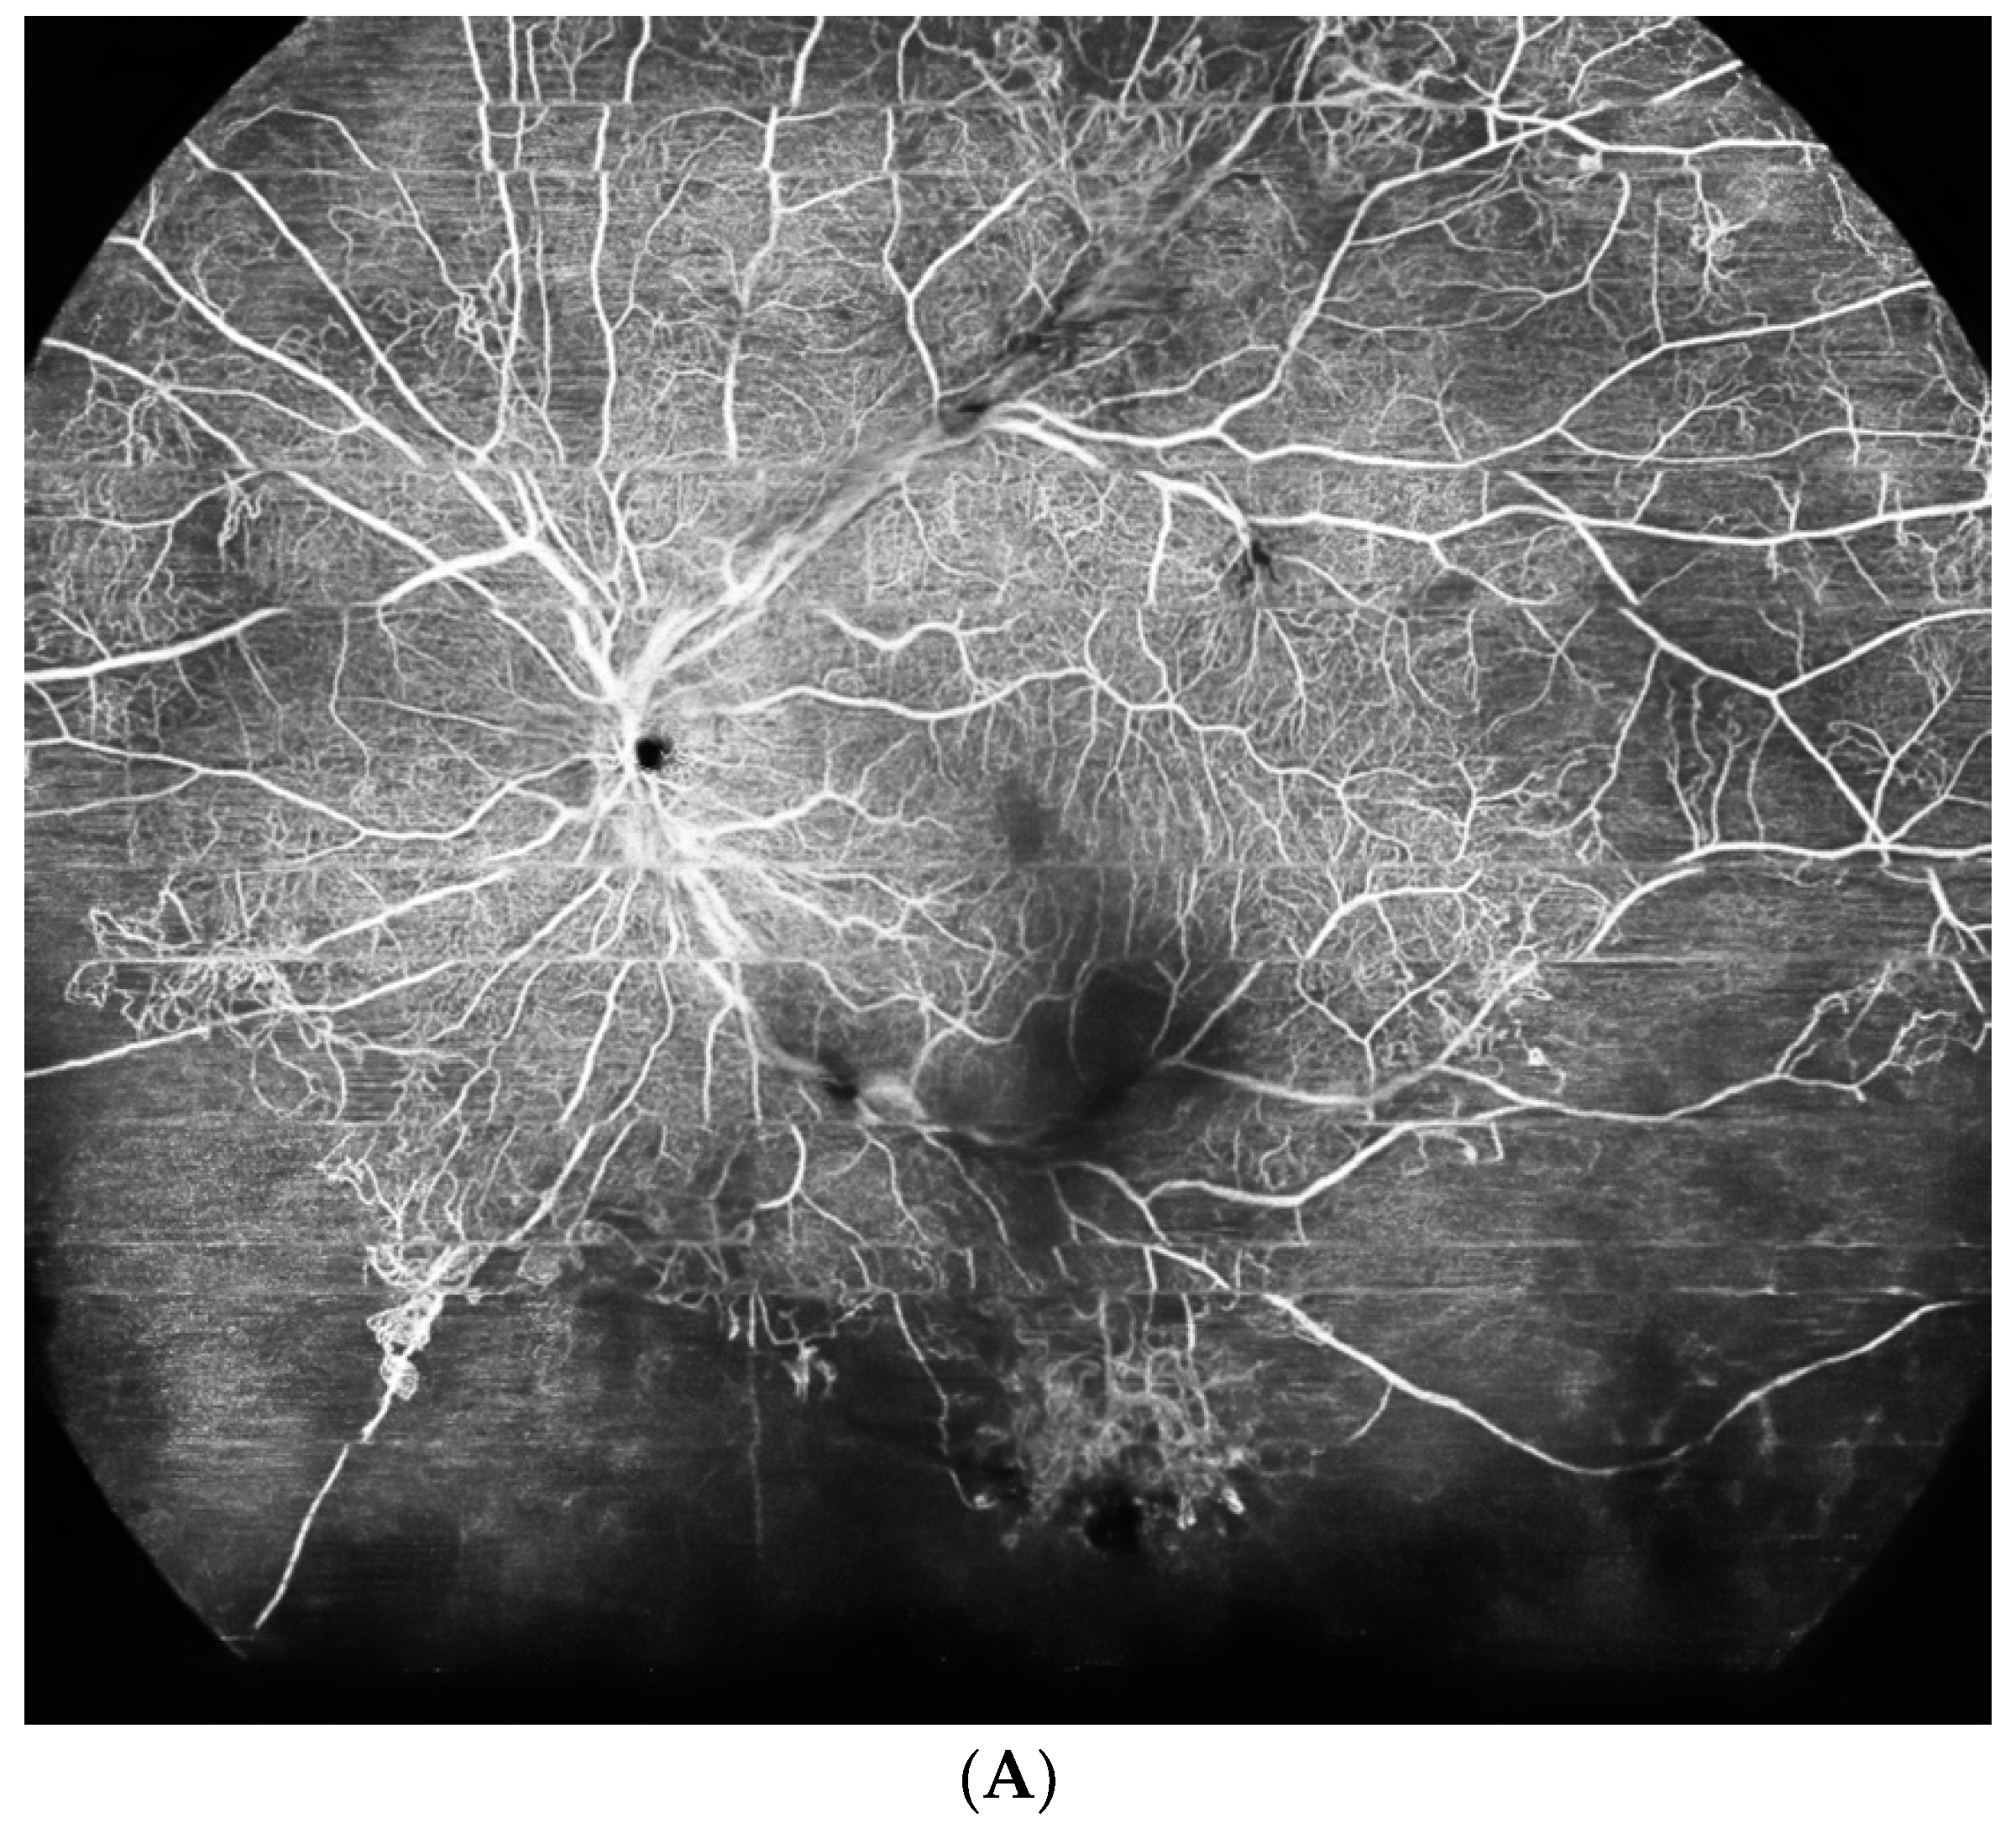

- Huemer, J.; Khalid, H.; Wagner, S.K.; Nicholson, L.; Fu, D.J.; Sim, D.A.; Patel, P.J.; Balaskas, K.; Rajendram, R.; Keane, P.A. Phenotyping of retinal neovascularization in ischemic retinal vein occlusion using wide field OCT angiography. Eye 2021, 35, 2812–2819. [Google Scholar] [CrossRef]